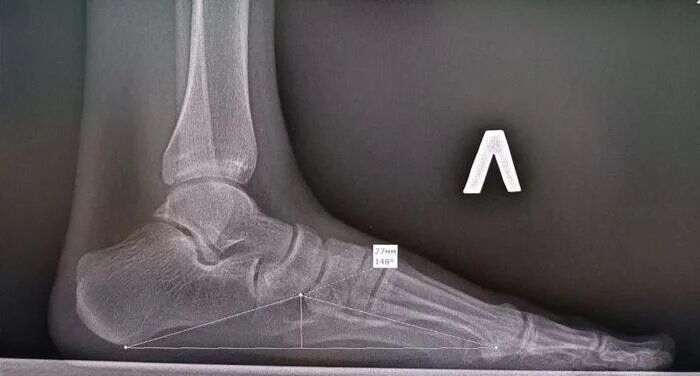

Рентгенография стоп с нагрузкой по Богданову — это специальное рентгенологическое исследование, которое является «золотым стандартом» для диагностики продольного плоскостопия. Его главная особенность в том, что снимки делают в положении стоя, под нагрузкой веса пациента, что позволяет оценить истинную форму и высоту сводов стопы в условиях, максимально приближенных к ходьбе. Основная цель исследования — получить точные геометрические параметры продольного свода стопы. Для этого рентгеновский снимок делают в боковой проекции, когда пациент стоит, перенося вес тела на исследуемую ногу. Это позволяет увидеть, насколько стопа уплощается под нагрузкой, и отличить функциональные изменения от структурных. Снимки выполняют в условиях естественной статической нагрузки, стоя на специальной подставке, в боковой проекции, с захватом 4–5 см голени, голень под прямым углом к стопе. Пациент исследуемой стопой стоит на деревянной подставке, вторую ногу отводит назад. Центральный луч направлен горизонт

Снимки выполняют в условиях естественной статической нагрузки, стоя на специальной подставке, в боковой проекции, с захватом 4–5 см голени, голень под прямым углом к стопе. Пациент исследуемой стопой стоит на деревянной подставке, вторую ногу отводит назад. Центральный луч направлен горизонтально через проекцию ладьевидно-клиновидного сустава.

Рентгенография стоп с нагрузкой призывника 18ти лет, высота продольного свода справа 23 мм, угол продольного свода справа 152 град., высота продольного свода слева 27 мм, угол продольного свода слева 148 град-соответствует двустороннему продольному плоскостопию 2 ст. Однако данный призывник проходил рентгенографию стоп с нагрузкой в детской пол-ке 3 мес. назад(т.к. на момент исследования не исполнилось 18 лет), где ему ставили продольное плоскостопие правой стопы 3 ст., угол продольного свода справа был -162 град. Было принято решение повторно провести рентгенографию стоп с нагрузкой.

Обращает на себя внимание визуально более выраженное уплощение продольного свода правой стопы при сравнении с предыдущим исследованием, можно предположить что вес тела не был перенесен на исследуемую стопу.

Высота продольного свода справа 16 мм, угол продольного свода 164 град. Высота продольного свода слева 28 мм, угол продольного свода 152 град. Заключение: Двустороннее продольное плоскостопие: 2(второй) ст. слева,3(третьей) ст. справа., соответствует категории годности к военной службе по ст.68(Плоскостопие и другие деформации стопы:) в-В(ограниченно годен к военной службе). В случае двустороннего продольного плоскостопия второй степени, категория годности по ст.68г Б-3(годен к военной службе с незначительными ограничениями).